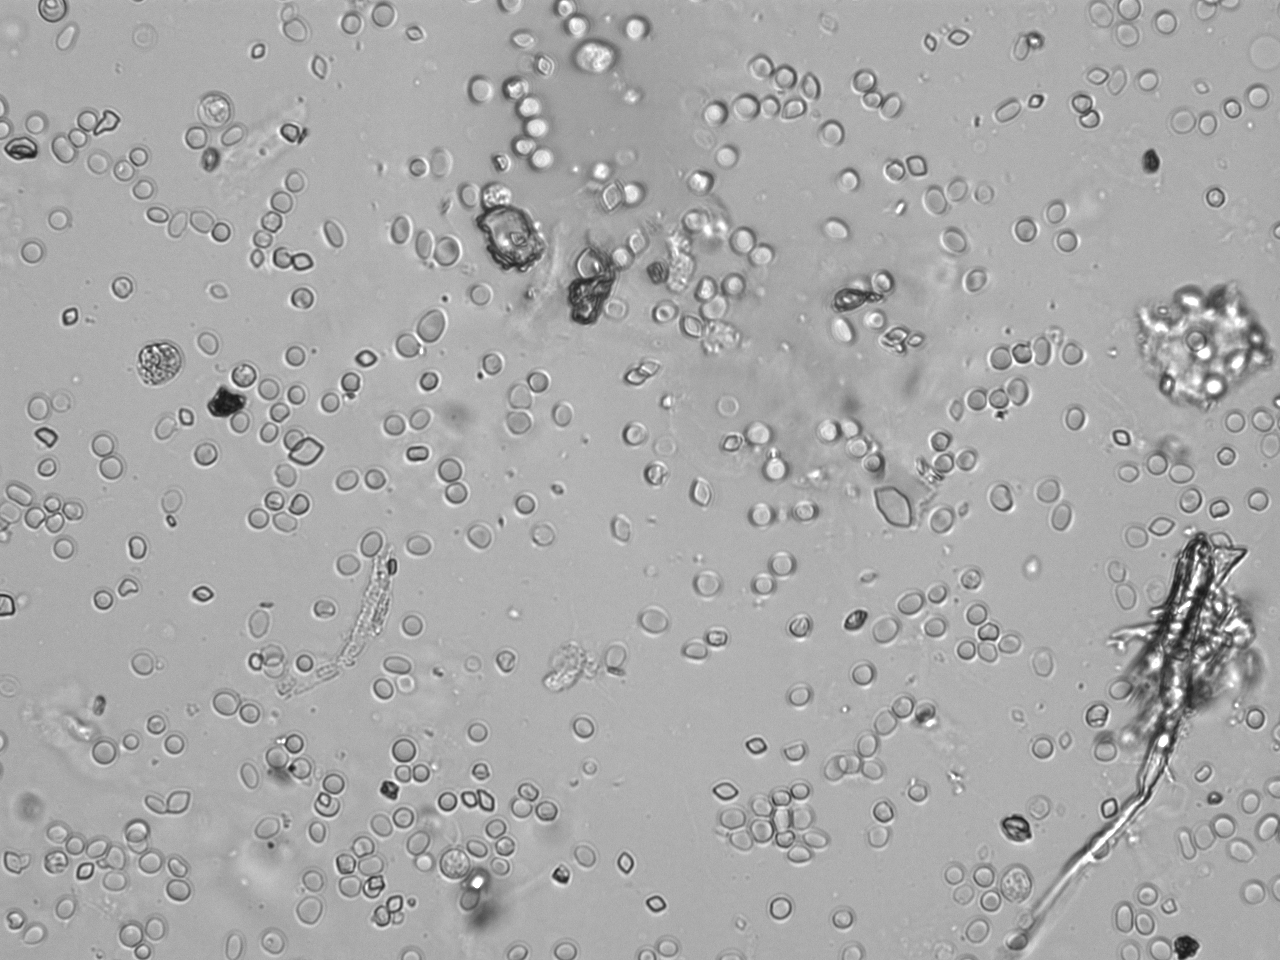

Urin-Feature: Harnskristalle_Rhomboid